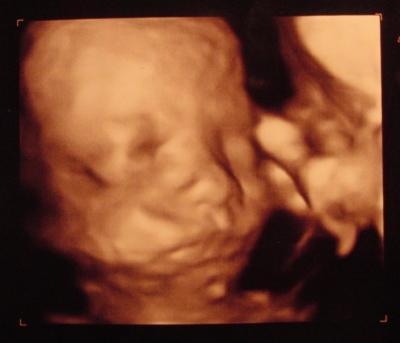

3d-Bild vom Zwerg

Hier mal ein Bild von unserem kleinen Moppel. Er wiegt schon 850g (ist damit fast 2 Wochen weiter). Daher musste ich zum Zuckertest, ist aber alles ok!

Bild zu 3d-Bild vom Zwerg - Forum für März - Mamis